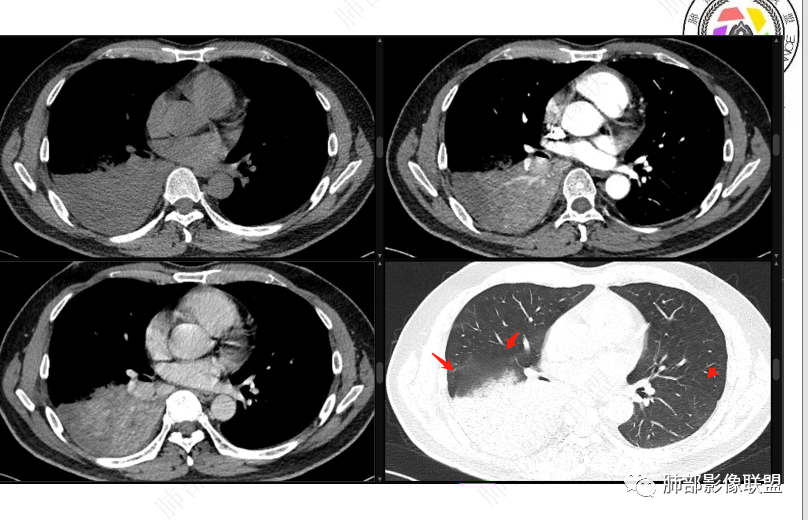

右肺下叶实变影,局部膨隆,边缘磨玻璃密度影,肺门区域明显强化考虑恶性,腺癌可能。

右肺下叶实变表现,强化和形态不考虑门口堵所致不张,枯树枝不明显,整个肺叶考虑肿瘤浸润,首先要考虑腺癌

右肺下叶实变,周围磨玻璃,近端支气管扩张,管壁凹凸不平,远端阻塞,可见粘液栓,不均匀强化,有低密度无强化影,其内血管显示尚可,考虑粘液腺癌,鉴别淋巴瘤

右肺下叶大片实变,密度不均匀,可见支气管充气征及粘液区,右肺下叶支气管内结节影,下叶支气管阻塞,病灶前下可见磨玻璃影,右侧积液,考虑粘液腺癌,鉴别类癌?

右下叶支气管狹窄,内见高密度强化结节,远端大片不张实变,实变内可见多发粘液拴,整体观察实变似有见缝就针的感觉,综和分析考虑粘液表皮样癌,其次考虑类癌

中央型肿瘤pk周围型肿瘤  。壮年男性,热咳一周伴气喘,中性白细胞升高,临床是个感染过程。支持中央型病变的证据:1  肺门明显强化结节 2 横s征  3 支气管粘液栓  4 主支气管变窄,似见冰山征      支持周围型病变:1 按叶段塑形  2 血管造影征  3 病灶内弥漫高强化  4 周围伴磨玻璃灶,但境界不清继发感染?误吸?综合 中央型肿瘤可能大:类癌》鳞癌

右肺下叶不张,右下肺门区高强化结节,似乎呈冰山征,首先考虑类癌可能

右下肺门似见一结节影,明显强化,远端支气管黏液栓,右肺下叶不张,考虑类癌,次之黏液表皮样癌 腺样囊腺癌

右肺下叶支气管见结节灶继发右肺下叶膨胀不全,右肺中央局部炎性改变,下叶支气管结节动脉期明星强化,静脉期强化减低,首先考虑肺鳞癌,鉴别类癌、粘液表皮样癌。